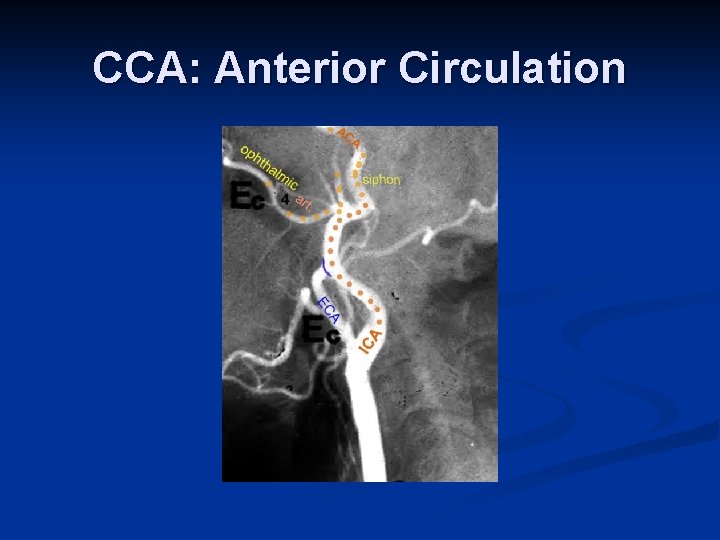

CCA: Anterior Circulation

ICA n n n n The internal carotid artery supplies the brain, the eye, the forehead, and part of the nose. It enters the cranial cavity via the carotid canal in the temporal bone. It gives off no branches within the neck region. The internal carotid artery supplies perfusion to the anterior and middle portion of the brain, the eye and its appendages and sends branches off to the forehead and nose. It originates at the carotid bifurcation and courses, via a number of curvatures, through the base of the skull into the Circle of Willis. The proximal-most portion of this vessel is rather bad bulbous and is referred to as the bulb. Distal to the bulb, the artery narrows and is referred to as the ICA proper. Anatomically, the ICA is distinct from the ECA in that there are no branches until it passes through the base of the skull. After coursing anteriorly to the transverse processes of the first three cervical vertebrae (C 1 –C 3), it enters the carotid canal of the petrous portion of the temporal bone. The intra-petrous portion of the ICA is also referred to as the cavernous portion of the ICA. After coursing through the base of the skull, its first branch arises, the ophthalmic artery, which supplies blood to the retina. (This is of clinical importance when discussing amaurosis fugax). At the base of the brain, the ICA gives rise to the anterior and middle cerebral arteries. The site of this branching is often referred to as the carotid siphon.